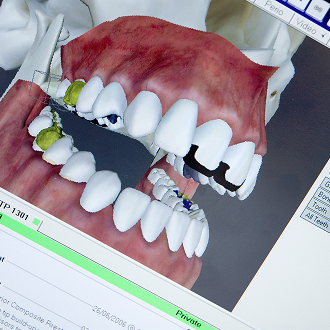

Treatment at our clinic is offered on a private basis and also to PRSI-qualified patients. Services include all routine dental treatment (examinations, cleanings, fillings etc.), cosmetic dentistry such as teeth whitening, bonding and porcelain veneers as well as more advanced procedures including the provision of crowns and bridges and dental implants.

We also provide specialist prosthodontic services here at Shelbourne so we can cater for those patients requiring extensive dental treatment such as full mouth reconstructions, severe wear cases and advanced cosmetic dentistry.

Listed below are some of the treatments and services we offer. We’ve also included several real life ‘case studies’ which demonstrate what can be encountered, and how we’ve managed the case.